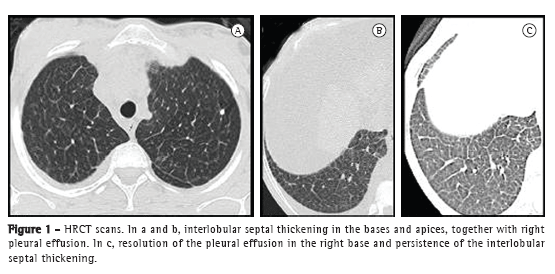

To the Editor:Niemann-Pick disease (NPD) is a rare lysosomal storage disorder that is generalized and severe, as well as being characterized by intracellular sphingomyelin accumulation caused by deficiency of sphingomyelinase activity.(1) From a respiratory standpoint, the various types of NPD, including type B, can cause progressive loss of pulmonary function, with suggestive radiological findings. We report the case of a 27-year-old female patient with type B NPD. The patient was initially referred for outpatient treatment in 2003, presenting with a history of hepatosplenomegaly and delayed psychomotor development since childhood. The diagnosis of NPD was confirmed by measuring peripheral leukocyte sphingomyelinase activity, which was found to be decreased (0.009 nmol h−1 mg−1 of protein; reference value, 0.745 nmol h−1 mg−1 of protein). Serology for HIV, hepatitis B, and hepatitis C was negative, as was serology for syphilis (venereal disease research laboratory test). In addition, ANF was negative. Gaucher's disease was ruled out because beta-glucosidase levels were normal. The patient developed ascites and complained of mild dyspnea, being referred to the pulmonology clinic. She underwent a six-minute walk test (six-minute walk distance [6MWD] = 396 m; predicted 6MWD = 724 m), showing intense dyspnea at the end of the test (modified Borg scale score = 9) but no oxygen desaturation (SpO2 = 97%). Spirometry results were suggestive of restrictive lung disease (FEV1 = 1.77 L [61% of predicted]; FVC = 2.07 L [57% of predicted]; and FEV1/FVC ratio = 85%). A chest X-ray revealed no pulmonary changes. An HRCT scan revealed interlobular septal thickening in the bases and apices, together with right pleural effusion (Figures 1a and 1b).

The patient developed chronic liver failure, having undergone orthotopic liver transplantation with splenectomy in September 2010. Four months later, there was complete resolution of the respiratory symptoms. At the time, a second pulmonary function test revealed improvement in the spirometric parameters (FEV1 = 2.53 L [80.7% of predicted]; FVC = 2.79 L [77.8% of predicted]; and FEV1/FVC ratio = 90.8%), and there was improvement in the 6MWD, which increased to 426 m, without desaturation (SpO2 = 98%). A second HRCT scan revealed resolution of the pleural effusion (Figure 1c) and persistence of the interlobular septal thickening.

The literature contains few reports of type B NPD patients submitted to liver transplantation, and little is known about the course of the disease after the procedure.(3) In this case report, the patient was asymptomatic after surgery, and it is likely that the respiratory complaints and the initial spirometric findings were related to liver involvement (pleural effusion, ascites, and pancytopenia due to hypersplenism). The CT findings obtained after liver transplantation revealed resolution of the pleural effusion and persistence of the interlobular septal thickening. The six-minute walk test was performed without continuous SpO2 recording, which could be more appropriate for a better analysis of the patient response to stress, and the diffusing capacity of the lung for carbon monoxide was not measured.(8)